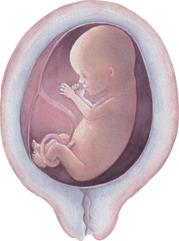

2. Monat: Der Embryo ist so groß wie ein Daumen und sieht schon wie ein winziger Mensch aus.

Der Embryo wächst in der Gebärmutter – die Zeit der Schwangerschaft

3. Monat: Der Embryo ist ca. 8 – 9 cm groß. Gesicht, Arme und Beine sind bereits entwickelt. Man nennt ihn jetzt Fetus.

Abb.3: Phasen der embryonalen Entwicklung

5. Monat: Die Mutter kann das Strampeln des Fetus wahrnehmen. Auf dem Kopf beginnen Haare zu wachsen.

7. Monat: Der Fetus ist vollständig entwickelt. Er muss nur noch wachsen.

9. Monat: Die Entwicklung des Fetus ist abgeschlossen. Die Geburt kündigt sich durch ein Ziehen in der Gebärmutter (Wehen) an. Die Fruchtblase, in der der Fetus herangewachsen ist, platzt und das Fruchtwasser fließt aus.

Der heranwachsende Embryo oder Fetus ist über die Nabelschnur mit dem Mutterkuchen (der Plazenta) verbunden. So wird er mit allen lebensnotwendigen Nährstoffen und mit Sauerstoff aus dem Blut der Mutter versorgt.

Geburt:

Durch starkes Pressen wird das ca. 50 cm große Baby aus dem Bauch gepresst.